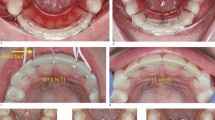

This paper presents a comparison of the outcome of two cases where teeth, avulsed in sporting accidents, were replanted in general dental practice and have been reviewed for 5 years. Avulsed teeth which were stored dry, had a long extra-alveolar period and were splinted for a longer period of time, ultimately underwent replacement root resorption (case 1). There was no evidence of resorption, after 5 years, in the tooth that was stored in the patient's own saliva and was replanted within 45 minutes of being avulsed (case 2). The replantation procedure for these two cases was based on recent literature, which is also reviewed in this paper, and a protocol for the management of avulsed teeth is suggested